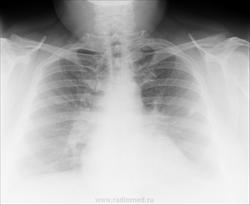

Женщина, 40 лет. Жалобы на длительный кашель.

Снимок мягкий, в легких по мне так чисто. Цепляет правый корень, если есть архив можно посмотреть, какой он был раньше. Если без динамики, то отпустила бы

Сложно судить о патологических изменениях из-за качества рентгенограмм. Возможно, тени, отмеченные Вами на боковом снимке есть и на прямой рентгенограмме ?

Отмеченные на правом боковом снимке тени, думаю, - легочный рисунок, не мтs. Тень, указанная коллегой NIL, вызывает подозрение и желание левого бока.

Она вызывает желание томографии)))

Саркоидоз легких и ВГЛУ, как рабочую версию.